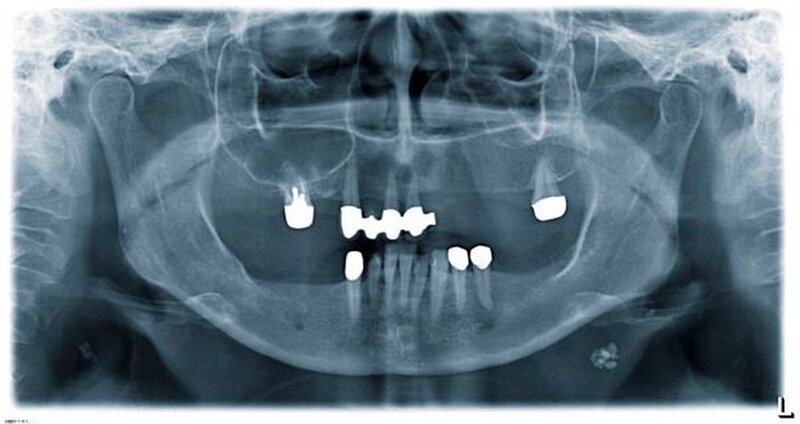

Zur genauen räumlichen Zuordnung der Verschattungen unterhalb der Incisurae semilunares wurde eine dentale digitale volumentomografische Untersuchung durchgeführt (Abbildungen 2 bis 4).

In der Zahn-, Mund- und Kieferheilkunde kommt den röntgenologischen Zufallsbefunden ein hoher Stellenwert zu, weil pro Orthopantomogramm durchschnittlich 3,9 pathologische Befunde erhoben werden können [Meyer-Oswald, 1981]. Die Einschränkungen einer Panoramaschichtaufnahme liegen in der fehlenden räumlichen Auflösung, in diskreten Artefakten bei Dichtesprüngen (Burn-out Effekt) und in Überlagerungen von knöchernen Strukturen.

In der konventionellen radiologischen Dia-gnostik erkennbare pathologische Veränderungen mit einer weitergehenden Notwendigkeit der Abklärung stellen eine mögliche Indikation für die 3-D-Röntgendiagnostik dar [AWMF, 2013].